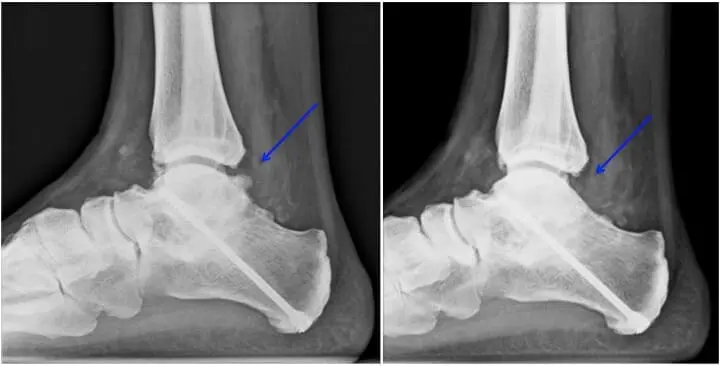

Des examens complémentaires, comme le scanner, restent indispensables à la recherche de lésions cartilagineuses, d’une arthrose débutante ou d’une souffrance ligamentaire,…

Il peut s’agir de séquelle traumatique, suite à des avulsions ligamentaires dans le cadre d’entorse ou des séquelles tendineuses avec rétrécissement des gaines tendineuses qui présente dès lors une inflammation. D’autre part, quand la douleur se localise sur la partie extérieure, il faut chercher d’autres origines de douleur.

Celle-ci peut être due à une inflammation de certaines structures articulaires chroniquement irritées par des mouvements répétitifs, souvent suite à un traumatisme, comme une entorse ‘banale’ ou une fracture de cheville. C’est d’autre part une lésion typique des ballerines surchargeant cette partie articulaire lors des mouvements en pointe « grande et demi pliée » .